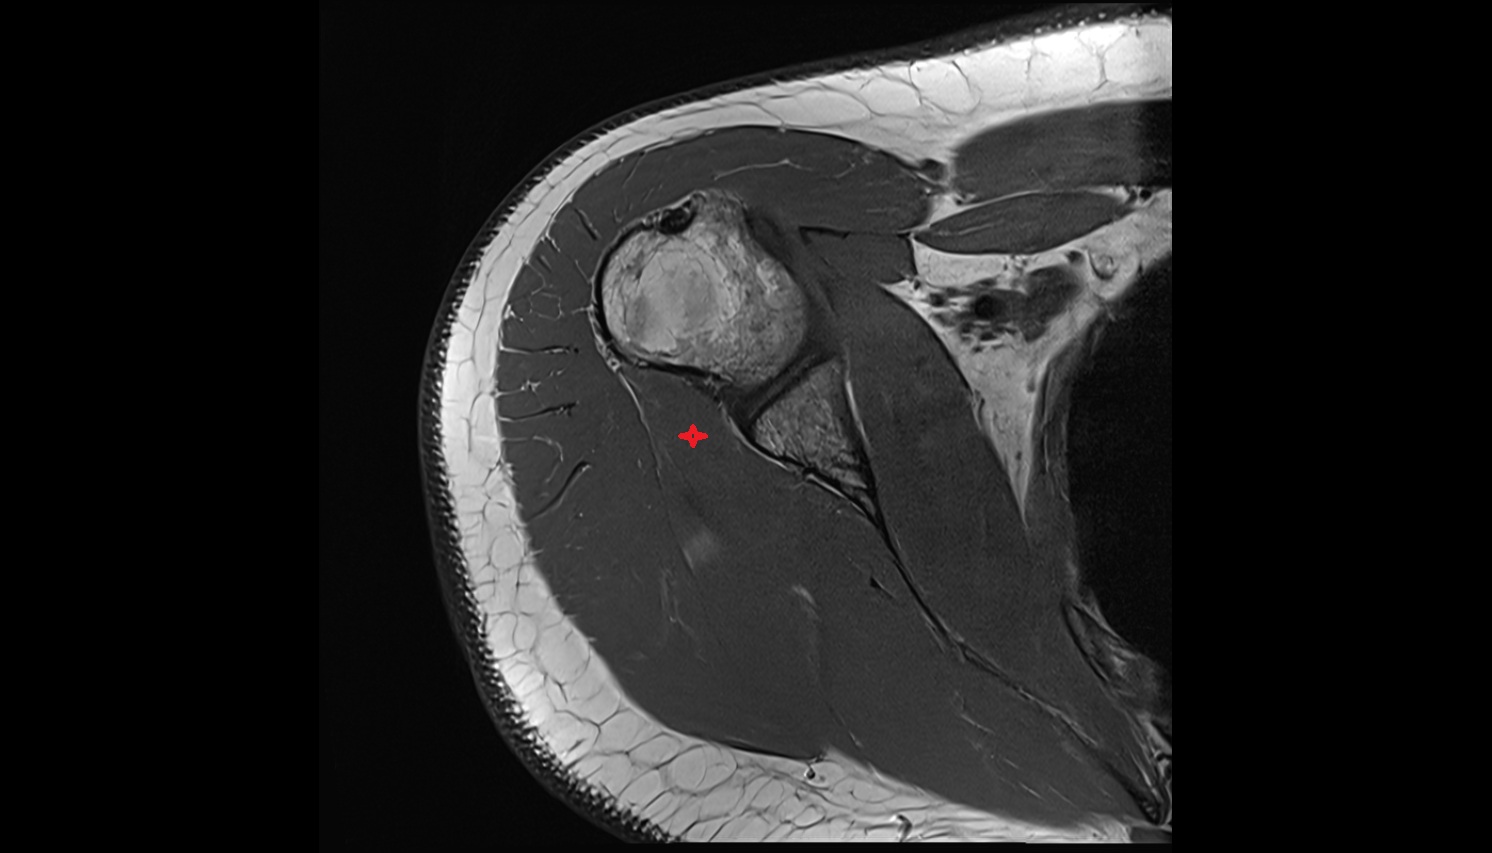

- Shoulder joint (glenohumeral joint)

- Glenoid fossa

- Glenoid process of scapula

- Glenoid labrum